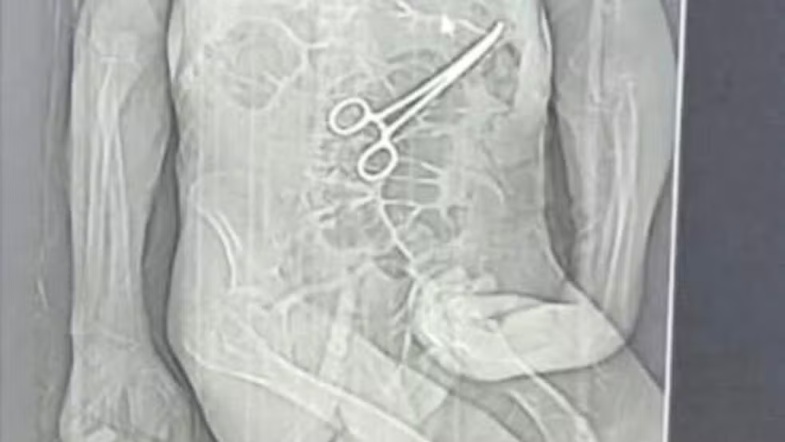

Tomografia mostrou pinça cirúrgica dentro do corpo do paciente após cirurgia | Foto: Reprodução

A família de Manoel Cardoso de Brito, de 68 anos, acusa o Hospital Municipal de João Pinheiro, no Noroeste de Minas, de erro médico após o idoso morrer na véspera do Natal. Segundo os parentes, uma pinça cirúrgica foi esquecida dentro do corpo do paciente após a primeira cirurgia, fato que, segundo os familiares, só veio à tona depois do óbito.

Em nota, a Secretaria Municipal de Saúde João Pinheiro confirmou que houve a retirada de um corpo estranho durante a cirurgia do paciente e alegou que Manoel estava em estado grave, com várias comorbidades.

Manoel permaneceu dois dias na UTI e depois foi transferido para o quarto. Durante a internação, apresentou sinais de dor e sonolência excessiva, o que preocupou a cuidadora contratada pela família. No dia 11, após suspeita de um AVC, foi feita uma tomografia. Consta ainda no boletim que, pouco depois, o paciente foi levado às pressas para uma nova cirurgia, sem que a família fosse informada sobre os motivos.